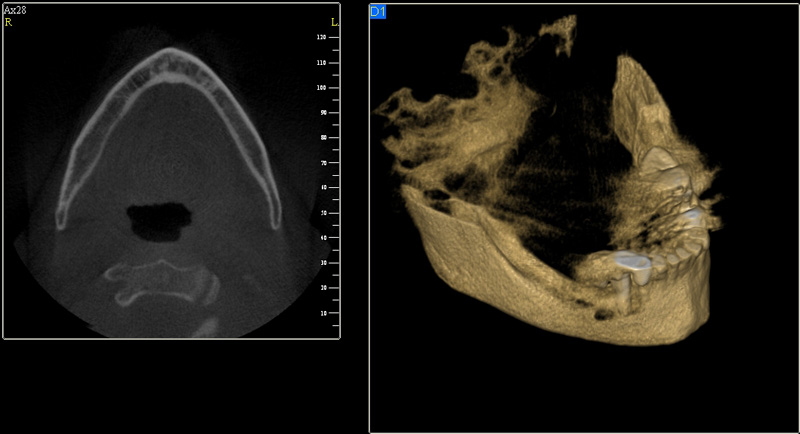

Tyto postupy nám umožní doplnit chybějící množství kosti v čelistech pacienta i zlepšit kvalitu kosti. Většinou se setkáváme s omezenou nabídkou kostní tkáně díky resorpčním (úbytkovým) procesům způsobených věkem či vytržením zubu, přítomností anatomických struktur jako je čelistní dutina, nervový kanál nebo patologických či poúrazových stavů - cysty, zlomeniny.

Při ztrátě molárů a premolárů v horní čelisti a jejich náhradě implantáty se často setkáváme s nedostatečnou vertikální nabídkou kosti pod čelistní dutinou, často doprovázenou i nedostatečnou horizontální nabídkou a sníženou kvalitou kosti

(v oblasti 2. premoláru v 50%, v oblasti moláru až v 80% případů nedostatečná kostní nabídka)